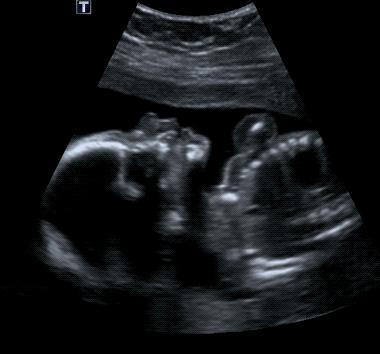

胎宝宝在打嗝时,准妈妈的腹部会感觉到有规律地一跳一跳,大约 2~3 秒钟一次,一般会持续 2~5 分钟,甚至 10~20 分钟。

有点像心跳的感觉,如果你把手放在跳动的地方,能摸到一动一动的感觉,非常奇妙。

△胎宝宝打嗝时妈妈肚子一跳一跳的